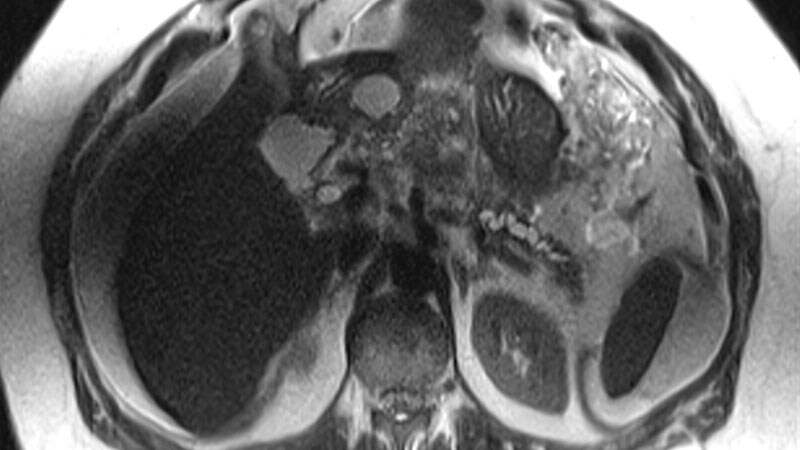

Metastatic Breast Cancer

Trop-2 Drug Conjugate May Trump Chemo in HR+, HER2- BRCA

SABCS 2023 Highlights Breast Cancer De-Escalation